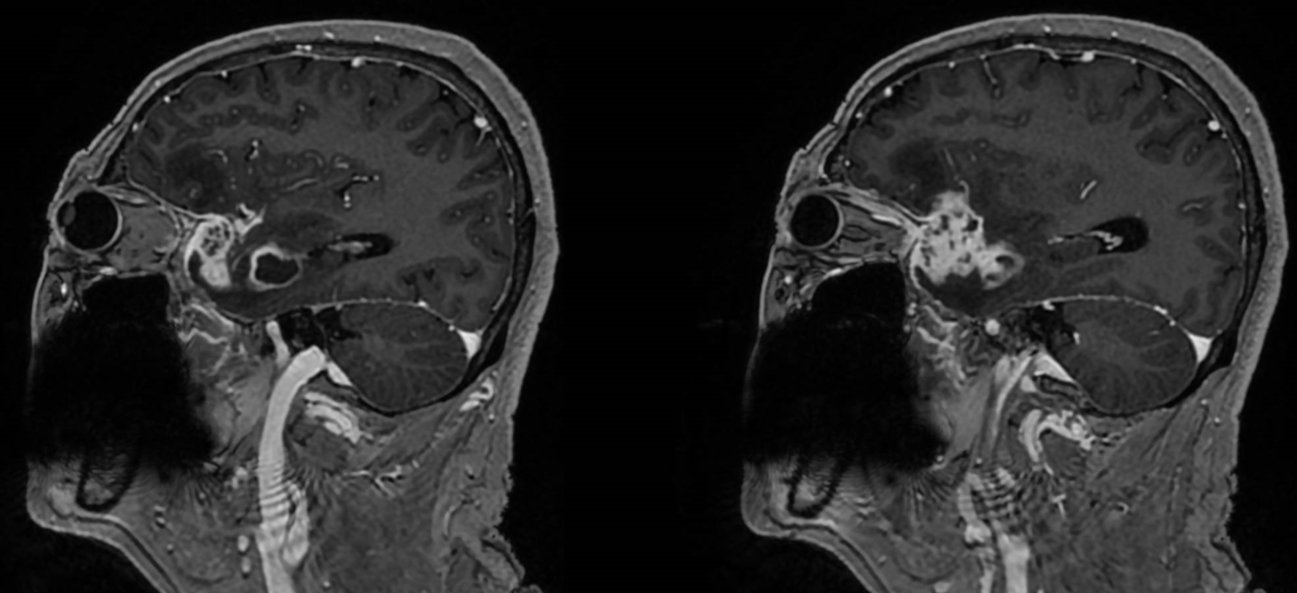

该患者入院后完善常规颅脑影像学检查,左侧颞叶病变,疾病性质不详,转移瘤、胶质瘤、炎症类疾病均不能排除,遂行PET-CT检查,提示左侧颞叶高代谢,淋巴瘤不能排除。组织MDT会诊建议可先行腰椎穿刺查脑脊液脱落细胞学、感染指标,若仍不能确诊,可进一步行开颅病灶切除,术中快速冰冻,根据冰冻结果决定手术手术策略。患者脑脊液脱落细胞学结果:较多淋巴细胞,少许单核细胞及个别中性粒细胞,未见异形细胞,脑脊液常规、生化、脑脊液培养未见细菌生长,诊断仍不能明确,且患者病情进展迅速,患者神志呈昏睡状态,颅脑MRI提示病变较前明显增大(影像学检查间隔两周),且水肿明显加重,遂行开颅病变切除术。术中见部分病变累及蝶骨嵴硬膜,病变质地硬韧,内有多个囊腔,囊内容物为黄色粘稠样脓性物质,留取囊液及实性部分送快速冰冻,在等待冰冻过程中,进一步探查见肿瘤侵犯左侧颞叶,该部位肿瘤质地相对软,无包膜,与周围脑组织无边界,血运不丰富,内有多个囊腔,且肿瘤侵犯侧裂池、颈动脉池,左侧视神经、颈内动脉、大脑中动脉均被病变包绕,且该处肿瘤质地偏硬韧。术中快速冰冻提示组织大片变性坏死,伴胶质增生及淋巴增生。结合病变质地及冰冻结果,考虑为非肿瘤性疾病,可能为炎性病变伴肉芽肿形成可能性大,且肿瘤质地硬韧,累及范围广泛,难以全切,遂行肿瘤大部分切除后结束手术。术后病理结果明确后予以伏立康唑、醋酸卡泊芬净抗真菌治疗。在治疗过程中患者先后出现脑出血、脑梗塞,最终因治疗周期长,花费高、效果不确定等因素,家属放弃治疗,于术后1月去世。